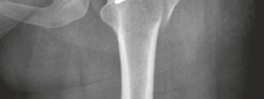

* Femoral Osteochondroplasty (for CAM Lesions):

* The prominent aspect of the femoral head-neck junction (CAM lesion) is resected using osteotomes or high-speed burrs. The goal is to restore the normal offset and sphericity of the femoral head, preventing further impingement.

* The resection should be precisely controlled to avoid over-resection, which can lead to femoral neck fracture, or under-resection, which results in residual impingement. The alpha angle is assessed intraoperatively.